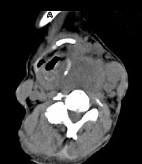

问题 女,64岁,发现双甲状腺肿大1月余,CT如图所示,最可能诊断为()

选项 A.结节性甲状腺肿 B.甲状腺腺瘤 C.甲状腺癌并淋巴结转移 D.甲状腺转移瘤 E.甲状腺结核

答案 C